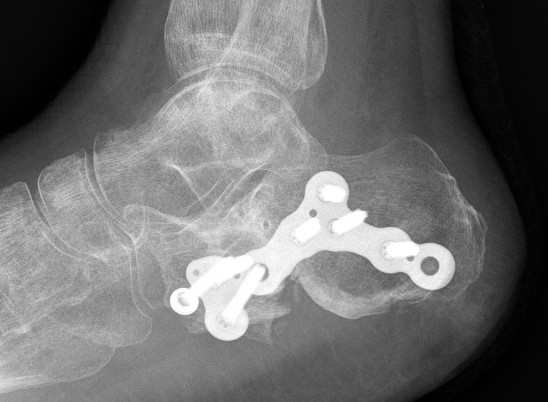

Primary Subtalar Arthrodesis

Indications

Type III / IV Sanders

Primary subtalar fusion

Patel et al J Foot Ankle Surg 2021

- systematic review 500 ORIF v 60 primary fusion for Type II/III

- better functional outcomes with ORIF

Buckley et al J Orthop Trauma 2014

- RCT of 31 patients with Type IV

- ORIF v primary fusion

- no difference in outcome